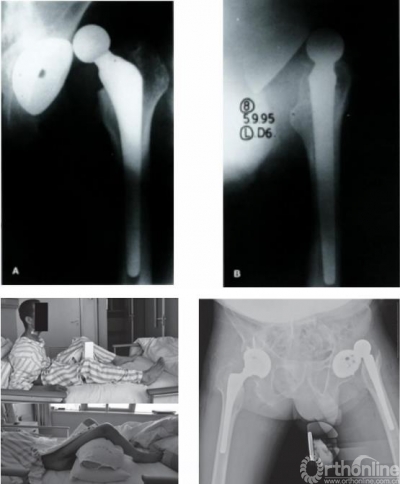

图7 AS引起THA术后脱位病例

手术时可根据后倾角度调整髋臼假体置入角度,减小外展与前倾角,防止术后脱位,增加站立位髋关节稳定性的同时,减少了假体与骨的接触面积,以适应变化的脊柱-骨盆力线,避免术后出现髋臼假体过度前倾,以及站立位时发生后方撞击、前方不稳甚至前脱位等并发症。对于合并脊柱后凸畸形的AS患者,除非畸形过于严重,应首选脊柱矫形术,再行THA。